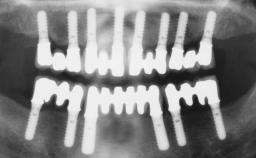

Conventional Loading of Eight Implants in the Maxilla and Final Restoration with a Full-Arch Gold-Ceramic FDP

# of Implants | 8 |

Type of Implants | One-Piece |